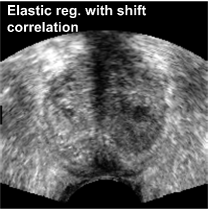

This measure requires less data to achieve statistical power compared to the two-dimensional Pearson correlation, but it is more general than the identity-assuming SSD with its zero DOF. It is invariant to low-frequency intensity shifts between the compared images, which is why we called it shift correlation 𝒟SCsubscript𝒟𝑆𝐶\mathcal{D}_{SC}. The invariant frequency range is controlled by the standard deviation σ𝜎\sigma of 𝒢𝒢\mathcal{G}. If σ𝜎\sigma gets smaller, the cropped range gets larger, and the registration convergence rate decreases and may even stall if only high frequency noise is left. When used with a multi-resolution solver on a Gaussian pyramid (cf. Sec. 4.5), which implicitly performs a low-pass filtering of the intensity variations on coarse resolutions, this approach transforms to a band-pass filtering on varying frequency bands. In this configuration it is sufficient to chose relatively small standard deviations, without risking registration inefficiencies. Fig. 7 illustrates the performance of the shift correlation model combined with the inverse consistency constraint.

Refer to caption

Figure 7: Intensity shift correlation model. Fig. (a) shows the floating volume, Fig. (d) the fixed volume (after rigid registration), Fig. (b) the elastic registration with the SSD correlation model and Fig. (c) shows the result with the intensity shift correlation model and inverse consistency constraints. All other parameters were identical for both registrations. The SSD driven registration is incorrect because of various local intensity shifts that are caused by the difference in probe pressure between the acquisition of the fixed and the floating images. The intensity shift correlation model correctly handles this problem and converges to the physically correct result.